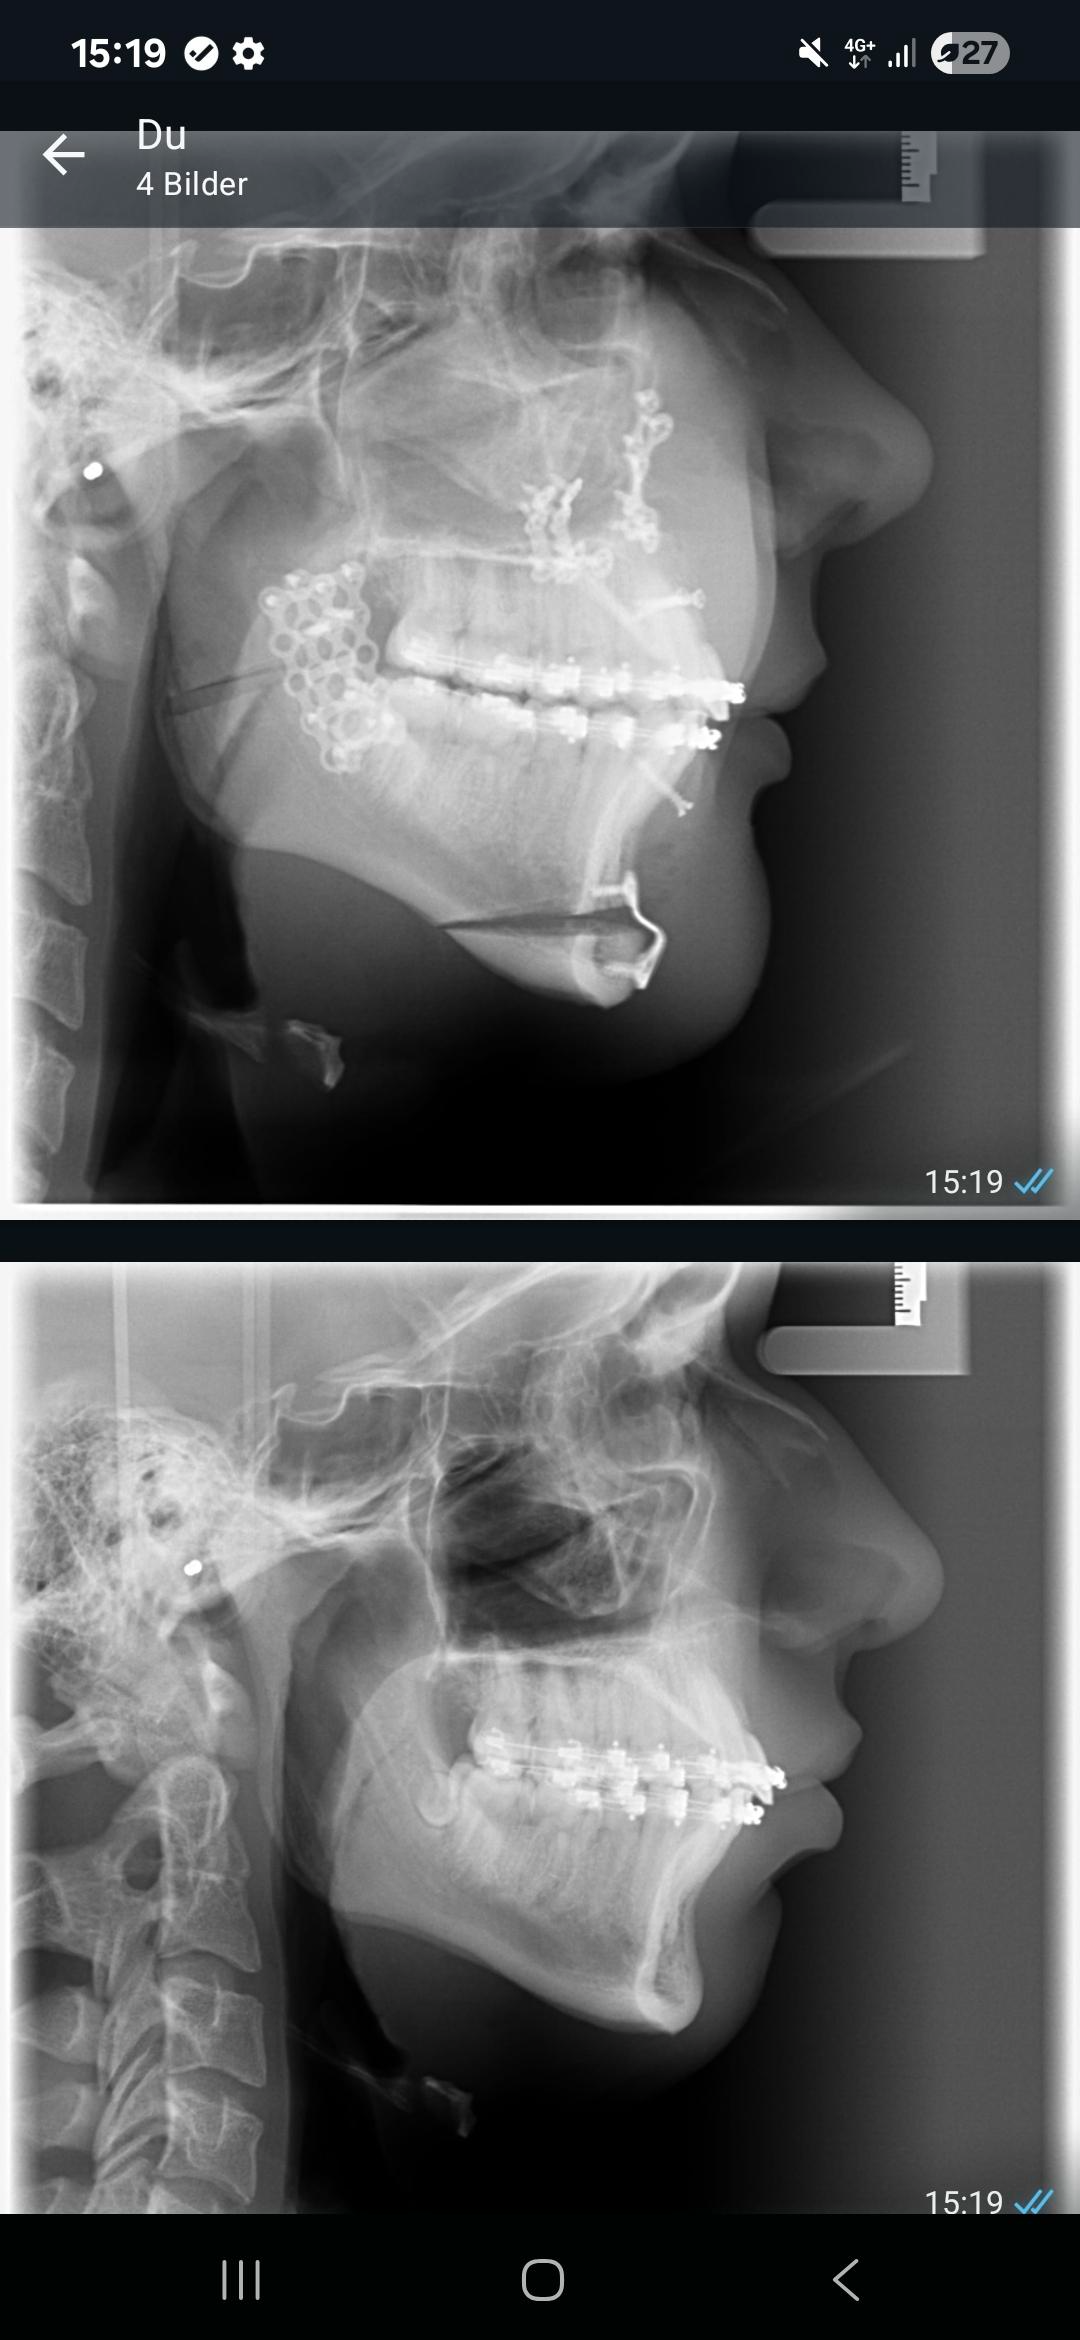

Can someone measure the before and after bimax? I got a very small CW

Digga dein gonial angle war vor surgery 120 grad und jetzt nach surgery 127 grad ???!?!

Denke liegt an kopfhaltubg beim röntgenbild, es wurde eine cw durchgeführt aber NICHT 8⁰. Was genau checkst du nicht? Hatte short face syndrome vorher deshalb macht cw schon sinn

Sachmal bist du aufm Kopf gefallen oder hast du Tomaten auf den Augen? Du siehst doch wie das Lineal an deinem Knochen sitz als Ankerpunkte? Deine Posture ist da irrelevant. Habe mir deine alten Fotos grad angeschaut und kann zu dem claim "shortface syndrome " nur fehldiagnose sagen. Nächstes mal bitte nach Surgeryplan fragen und unabhängig evaluieren lassen bevor du irgend nen rdm shit freestylest nur weil "Der Arzt das sagte das es so ist".

Ok bro, trotzdem ist mein short face syndrome behoben (was ich definitiv hatte, mein lower third war sehr kurz), und meine Seite ist definitiv um längen besser als vorher also war sie bimax kostenlos zu machen doch keine schlechte Entscheidung oder?